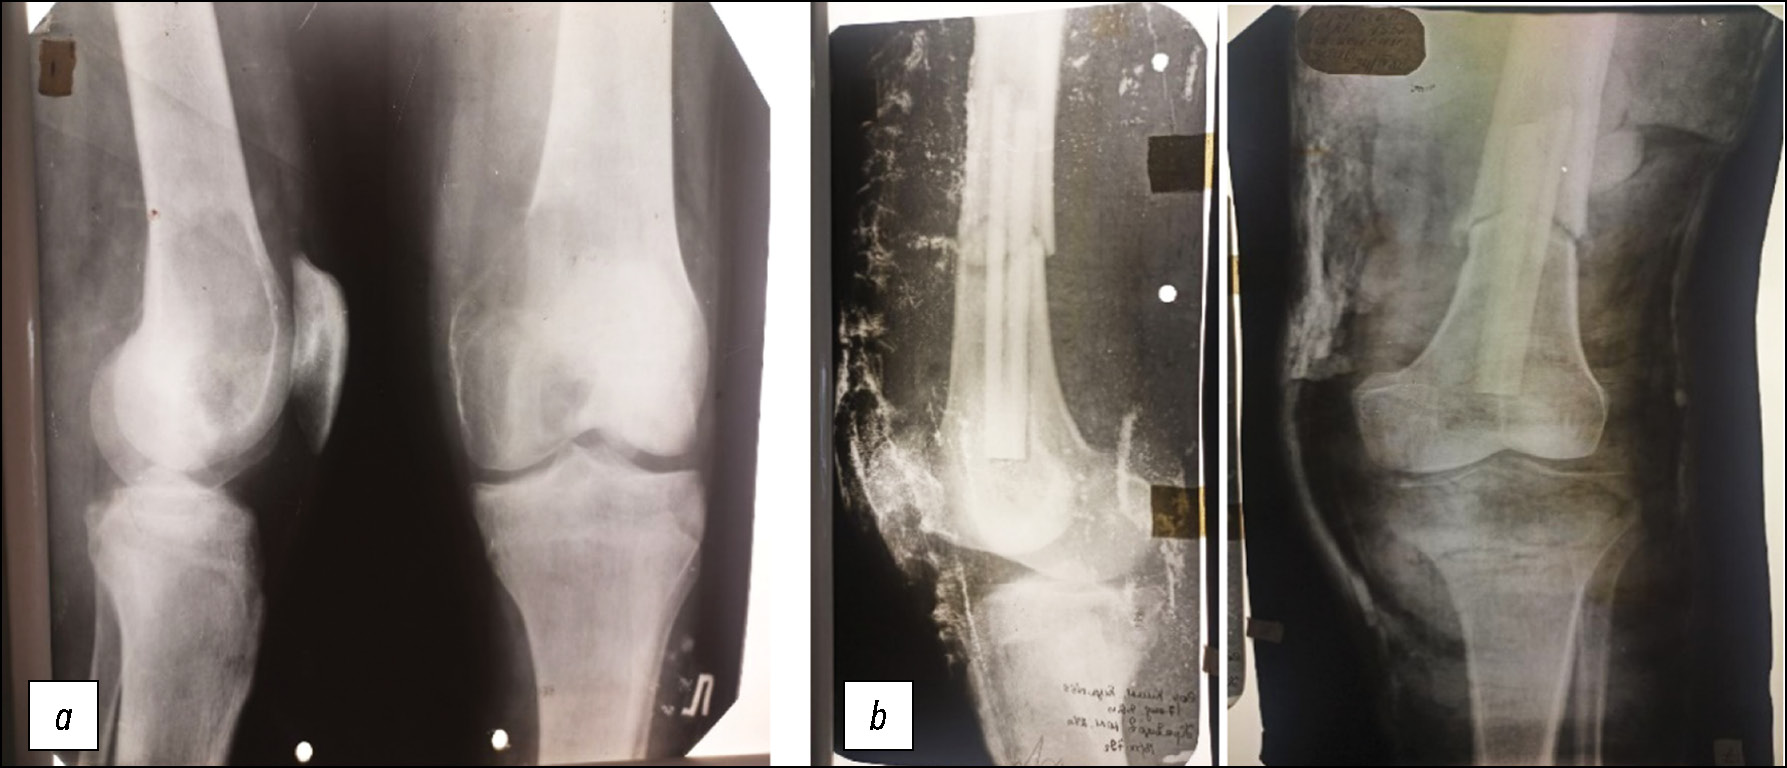

В Центральном институте травматологии и ортопедии (ЦИТО) им. Н.Н. Приорова была диагностирована остеобластокластома дистального отдела левой бедренной кости (по современной классификации — гигантоклеточная опухоль) (рис. 1а), и пациента госпитализировали в городскую клиническую больницу № 59 г. Москвы, в клинику травматологии и ортопедии, которую возглавлял лауреат Государственной премии СССР профессор Айдын Саларович Имамалиев, заведовавший кафедрой травматологии, ортопедии и военно-полевой хирургии Московского медицинского стоматологического института им. Н.А. Семашко и лабораторией консервации органов и тканей ЦИТО им. Н.Н. Приорова.

Рис. 1. Рентгенограммы коленного сустава: а — до, b — после аллопластики дистального конца бедренной кости.

Fig. 1. Radiographs of the knee joint: a — before, b — after alloplasty of the distal end of the femur.

11 декабря 1979 года пациенту была произведена резекция дистального суставного конца левой бедренной кости на протяжении 12 см с замещением дефекта аналогичным аллотрансплантатом, консервированным при температуре минус 70 градусов. Как показали экспериментальные исследования и клинические наблюдения, проведённые А.С. Имамалиевым, этот режим консервации был наиболее благоприятным для сохранения биологических свойств трансплантата, его сращения с материнской костью, предотвращения лизиса и сохранения прочности. Трансплантат зафиксировали к материнской кости внутрикостно кортикальным штифтом (рис. 1b). Связочный аппарат сустава восстановили с помощью лавсановой ленты. В послеоперационном периоде 3 дня осуществляли дренирование области операции, а после заживления раны был проведён курс ЛФК на функциональной шине. Через 3 недели после операции пациенту наложили кокситную гипсовую повязку и выписали его на лечение по месту жительства с рекомендацией продолжить иммобилизацию до 6 месяцев.